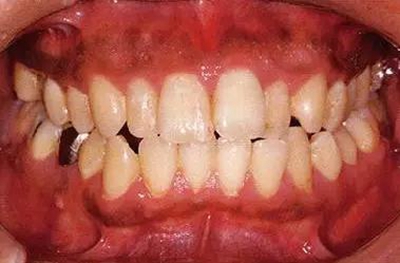

14歲男性牙齦炎的臨床圖像

14歲男性。刷牙狀態(tài)不佳。整顎浮腫性發(fā)紅、腫脹且刺激出血。牙頸部有早期齲(白斑)。